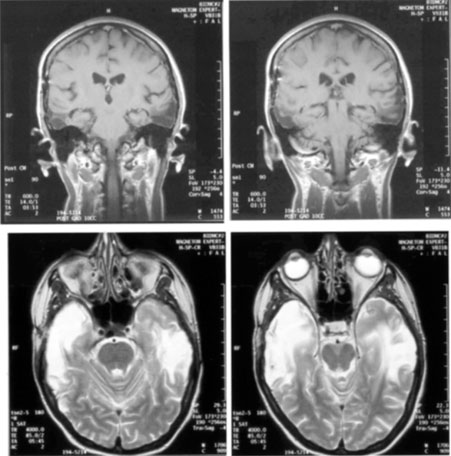

OPTIC RADIATIONS

The optic radiation may be affected anywhere in its course (see Chapter 4); the type of visual field defect reflects the site of damage. Ischemic or hemorrhagic lesions of the internal capsule affect the optic radiation while it is still a relatively compact bundle, usually causing a complete homonymous hemianopia. A similar defect can arise from damage close to the termination in striate cortex (Fig. 5). Lesions of the ventral fibers in the anterior temporal lobe cause a contralateral superior visual quadrant defect (Fig. 6). Most often this defect aligns on the vertical meridian, with variable extension toward the horizontal meridian and central vision.33 Lesions of the dorsal fibers in the parietal lobe cause an inferior visual quadrant defect (Fig. 7). Because there is no sharp demarcation of the dorsal fibers from the ventral fibers in this portion of the posterior pathway, the defect seldom aligns along the horizontal meridian.33 Overall, quadrantanopia is more frequent with lesions of striate cortex.33 Lesions of the temporal lobe more than 8 cm posterior to its anterior tip can affect both upper and lower radiations. Small lesions also may affect certain portions of the radiations and spare others; for example, damage to the midportion of the optic radiation can mimic the sectoranopias of LGN lesions (Fig. 8).34 Although there can be some incongruity to the visual field defects of optic radiation lesions, this is less marked than the incongruity with optic tract lesions.

Fig. 6. Lesion of temporal optic radiation. Left superior quadrantanopia, respecting horizontal meridian (A), from infarct of right medial temporal lobe, in posterior cerebral artery territory (B). (From Rosen ES, Eustace P, Thompson HS, Cumming WJK [eds]: Neuro-Ophthalmology. London: Mosby, 1998.)

Fig. 7. Lesion of parietal optic radiation. A 35-year-old woman with 3 weeks of left-sided headache. A. Visual fields showed partial right inferior quadrantic defect. B. MRI showed infarct of parietal lobe, involving optic radiations. (From Rosen ES, Eustace P, Thompson HS, Cumming WJK [eds]: Neuro-Ophthalmology. London: Mosby, 1998.)